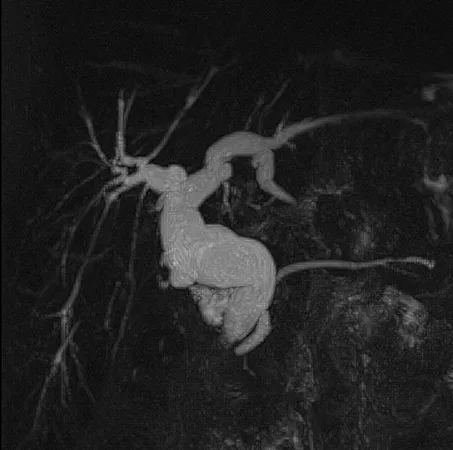

Le diagnostic positif de maladie de Caroli repose sur la cholangio-IRM. Celle-ci met en évidence de volumineuses dilatations kystiques des VBIH, en communication avec le reste de l’arbre biliaire (figure 7A). Il est fréquent de visualiser des calculs au sein des dilatations kystiques (figure 7B). Après injection de produit de contraste, il est classique de visualiser un vaisseau réhaussé (branche de la veine porte ou de l’artère hépatique) au sein de la dilatation kystique (figure 7C). Ce signe radiologique dit « central du point » (central dot sign), témoin d’une malformation de la plaque ductale, est pathognomique de la maladie de Caroli. Dans la maladie de Caroli isolée, les dilatations kystiques peuvent être localisées au niveau d’un lobe ou d’un segment hépatique, alors qu’elles sont généralement diffuses dans le cadre du syndrome de Caroli (tableau 1). Concernant le diagnostic de FHC, l’apport de l’imagerie est plus limité, mais permet d’évaluer la présence de signes radiologiques d’HTP (splénomégalie, voies de dérivations porto-systémiques). Il peut néanmoins exister des lésions biliaires associées à la FHC isolée sans syndrome de Caroli, à type de cholangite ou d’augmentation de volume de la vésicule biliaire (23).

Figure 7 : Visualisation par IRM hépatique de lésions caractéristiques de maladie de Caroli : dilatation kystiques (étoiles) des canaux biliaires intra-hépatiques (A) ; présence de calculs (flèches) au sein des dilatations kystiques biliaires (B) ; central dot sign : vaisseau réhaussé au sein d’une dilatation kystique (flèche) (C)